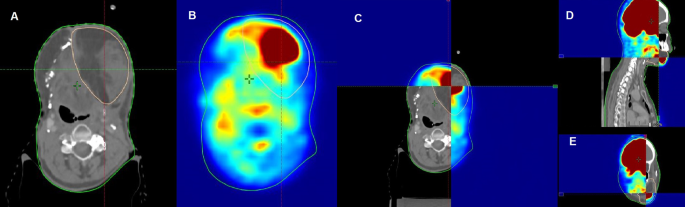

For adjuvant RERT, the preoperative PET CT was similarly fused with CTsim, involving the same matching procedure (Fig. 2). The auto-contoured GTV volume was compared to the post-operative bed (CTV) contour on CTsim to ensure inclusion of suspicious volumes, subsequently receiving a 5 mm PTV margin.

Following dental prophylaxis, patients underwent RT planning, including a contrast-enhanced CT scan in the treatment position with laser alignment to the markers. Head and neck CT scans, with 2.5–3 mm slices, were taken using a helical CT scanner up to the carina level after intravenous contrast injection. CT images were transferred as DICOM files to the contouring workstation, Eclipse planning system. The OARs were contoured per Radiation Therapy Oncology Group (RTOG) contouring guidelines. For definitive RERT, gross tumor volume (GTV) was mapped based on clinical findings, radiological imaging, and direct/indirect laryngoscopy findings, with PET CT assisting in GTV delineation. The PET CT, initially used for disease diagnosis, guided target delineation (Fig. 1). The DICOM files underwent rigid registration with CTsim as the target image and CTpet as the source image, initially auto-matched and manually refined. Using the PET adaptive threshold technique, the SUVmax of the tumor is set for contouring purpose. Now the PET components were overlaid on CTsim to define disease, using a 40% SUVmax threshold algorithm for GTV delineation, followed by slice-by-slice validation to include suspicious, contrast-enhancing regions. A 5 mm planning target volume (PTV) margin was standardly added to the GTV in re-irradiation.